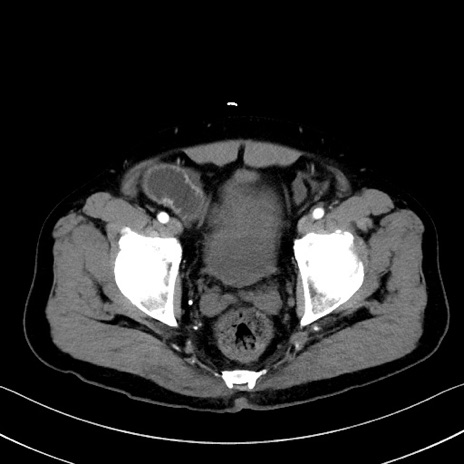

症例35(横断像)

【症例】70歳代 男性

【主訴】腹部膨満、嘔吐

【現病歴】昨日より腹部膨満感出現。本日増悪し、仙痛出現。嘔吐あり、受診。

【既往歴】糖尿病、胆摘後

【身体所見】BP 149/80mmHg、HR 74/min、BT 35.9℃、腹部:膨満、軟、圧痛なし。腸雑音減弱あり。上腹部正中切開瘢痕あり。

【データ】WBC 13500、CRP 1.72